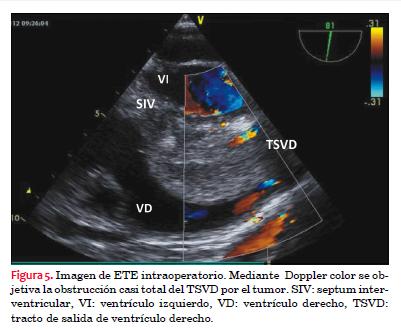

El procedimiento fue monitorizado con ecocardiograma transesofágico (ETE) intraoperatorio, con el que se confirmó la resección total del tumor, sin daños a nivel del SIV. La plastia de De Vega fue exitosa. Las figuras 5 y 6 corresponden a imágenes del ETE en las que se observa el tumor protruyendo en el TSVD y obstruyendo prácticamente la totalidad del mismo. Mediante Doppler color se evidenció el escaso flujo que pasaba por la periferia del tumor (figura 5).

En nuestro caso, a nivel del VD encontramos una masa adherida, mediante un pedículo, al tercio medio del septum interventricular, muy móvil, que protruía hacia el TSVD generando un gradiente de grado severo. Como lo muestran las figuras 5 y 6, se trata de una masa ovoidea, de gran tamaño (40 por 32 mm), de bordes lisos, ecogenicidad heterogénea, con algunos puntos de calcificación. Destacamos la importancia de este estudio, ya que nos aproxima notablemente a la naturaleza del tumor y nos permite planificar una correcta cirugía. No obstante, debemos de recordar que el diagnóstico definitivo es anátomo-patológico.